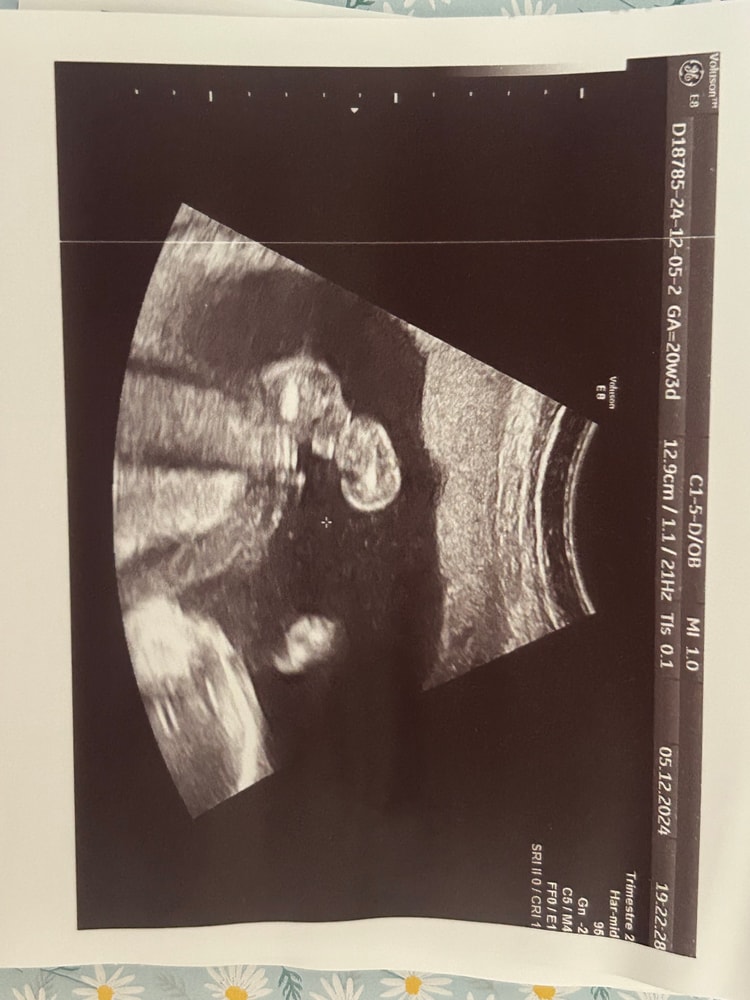

Arina в Клуб беременных 8 месяцев Пол малыша. Тут 20-21 нед🐣 Пол малыша Всем привет! Подскажите, пожалуйста 🙏🏻 это ведь мальчик? :) Посмотрите еще 20 записей на эту тему Лучший ответ Мама Лиля Пацан 23.03.2025 Ответить Отменить Ответить Лера Это мальчик 23.03.2025 Ответить Ольга На девочку похоже, если я правильно вижу))) 23.03.2025 Ответить Ольга Ольга , хотяяяяяя.... На последней фотке мальчик 23.03.2025 Ответить Сабрина я не разбираюсь, но интуитивно кажется что мальчик 🤔 23.03.2025 Ответить Лариса Тоже кажется, что мальчик. А врач кого предположил? 23.03.2025 Ответить Светлана По последней фотке- мальчик 23.03.2025 Ответить Пришел анализ на определение пола 😍 Пол ребенка Чаты Беременных Выберите чат: Январята-2026 Февралята-2026 Мартята-2026 Апрелята-2026 Майчата-2026 Июнята-2026 Июлята-2026 Августята-2026